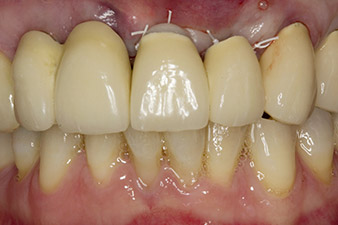

Fig. 1 : Les premières radios ont révélé une restauration par couronne jumelée à remplacer. Une fois la restauration retirée, les dents 21 et 22 ont involontairement été extraites en même temps.

Lorsque le patient s'est présenté pour la première fois, les dents 21, 22 et 23 avaient été restaurées il y a 19 ans à présent, par des couronnes jumelées collées sur les implants en position 12/11 à l'aide d'une attache

(cf. Fig. 2).

La radio a révélé une perte osseuse horizontale autour des dents 21 et 22 (Fig. 1). Lorsque la structure de couronne a été retirée, ces dents ont involontairement été extraites en même temps.

La dent 23 présentait une fracture coronaire horizontale et un matériau de reconstitution du moignon et de scellement des tenons a été utilisé à titre de restauration temporaire. L'objectif était de poser un bridge en oxyde de zirconium sur les implants existants aux positions 12 et 11 et de poser deux nouveaux implants aux positions 22 et 23.